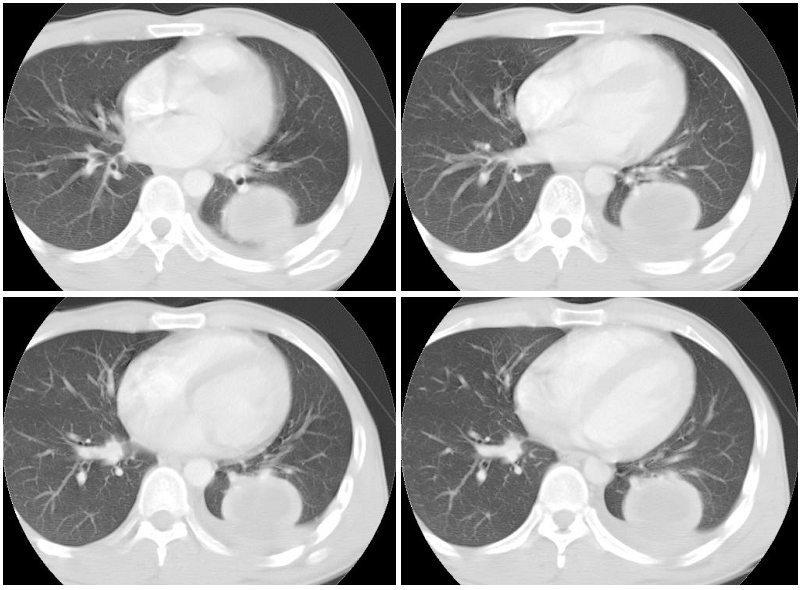

男性,34岁,咳嗽,胸痛一个月,左下肺呼吸音清。分别是肺窗(1-2),纵隔窗(3),增强动脉期(4),平衡期(5),平扫ct值为40-50hu,增强后厚壁达到80-100hu, [/color]

左下肺可见类圆形高密度影,可见双环征,增强后,壁强化明显,内低密度影未见强化,同侧胸腔积液,左下肺脓肿。治疗后复查。

左肺下叶类圆形肿块,呈典型的环形强化,累及胸膜,少量胸腔积液